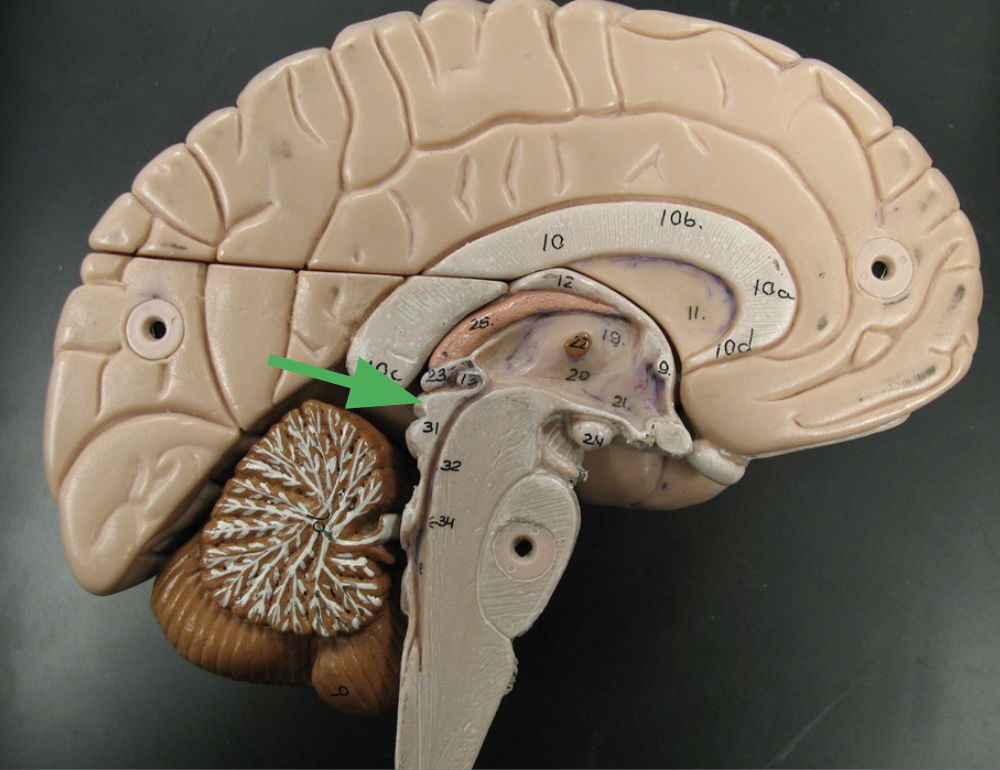

What does the arrow indicate?

What happens in this area?

Cerebral aqueduct

Connects the third and fourth ventricles, allowing cerebrospinal fluid to flow between them.